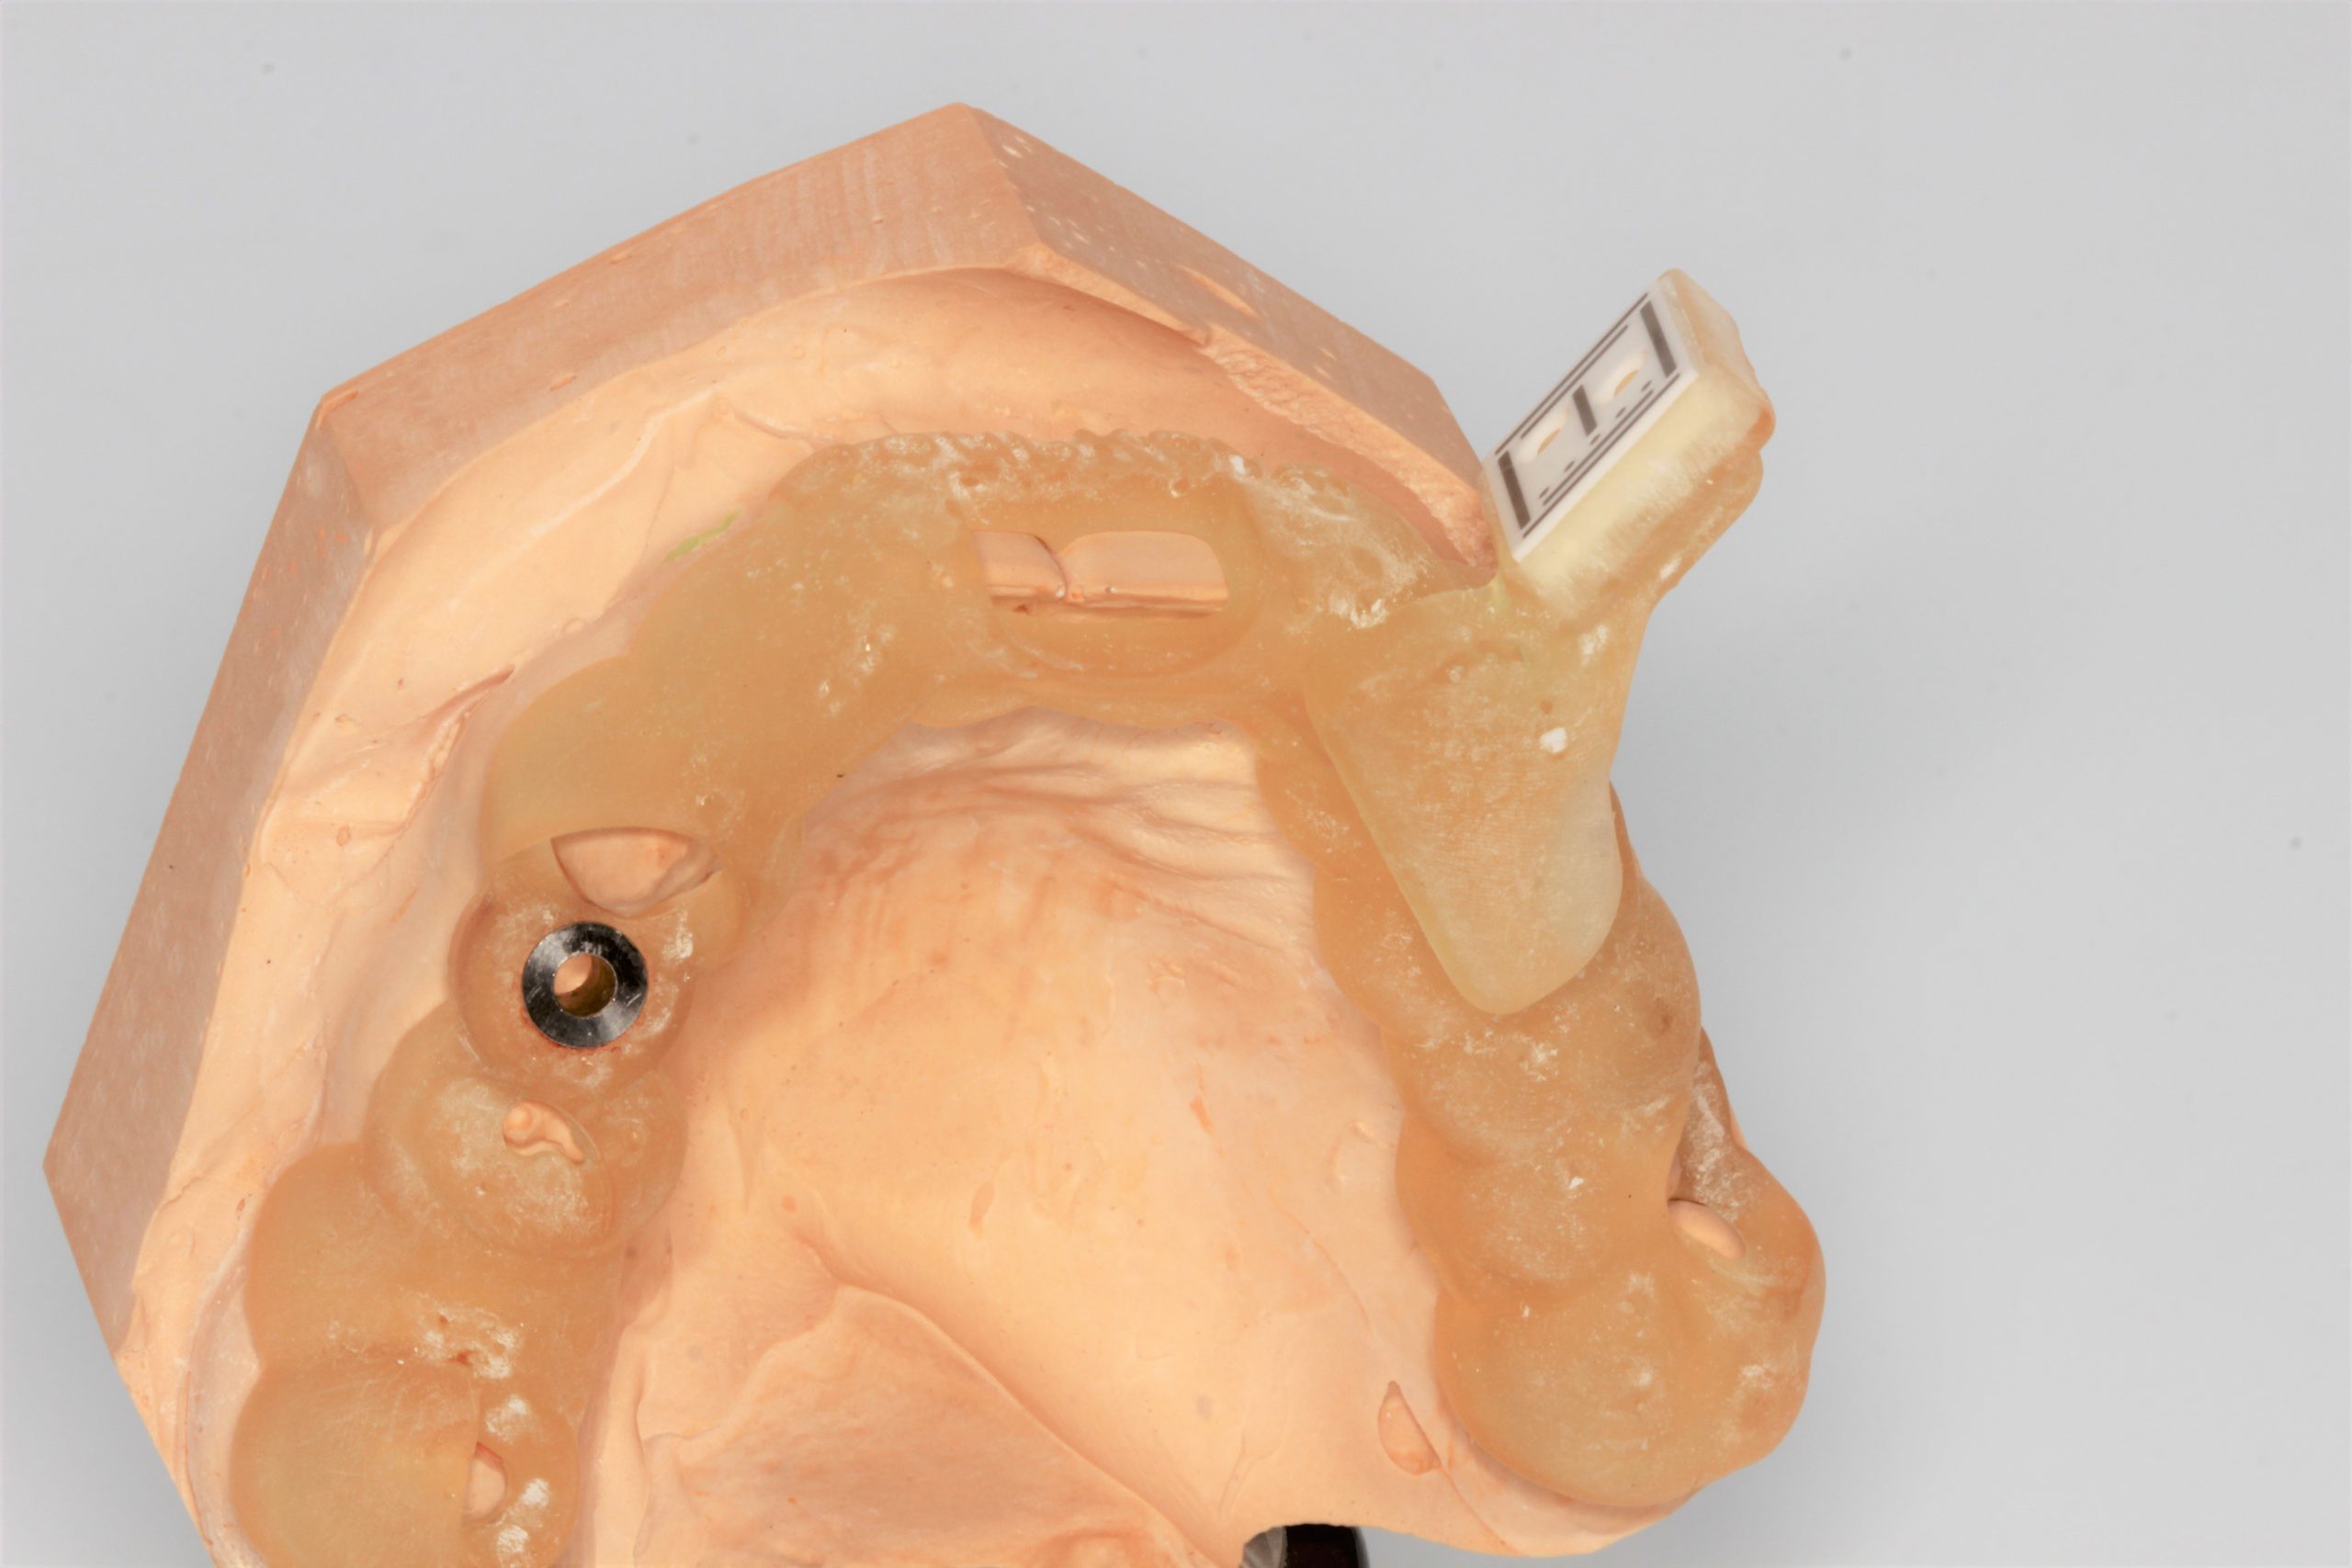

Die auf Zähnen abgestützte Schablone enthielt eine Führungshülse für die statische schablonengeführte Pilotbohrung sowie einen Halter für den Sensor der dynamischen Navigation. Die Schablone wurde mittels 3D-Drucker hergestellt.

Röntgenkontrollaufnahme nach der Implantation. Das Implantat wurde inseriert wie geplant.